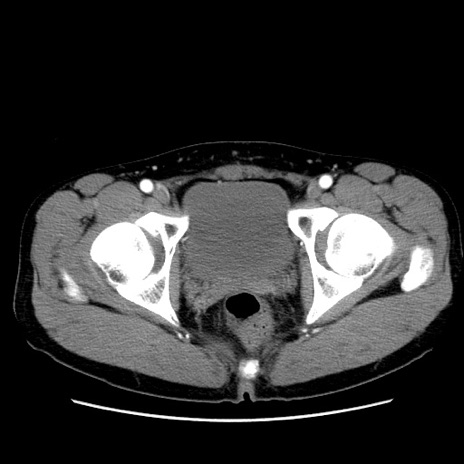

症例36(横断像)

【症例】20歳代 男性

【主訴】心窩部痛

【現病歴】今朝より上腹部痛あり。一旦軽快していたが再度出現したため救急要請。昨日夕に白身の魚を含む刺身を食べた。

【身体所見】BP 136/89mmHg、HR 74/min、BT 37.0℃、腹部:膨満、軟、心窩部に圧痛あり。反跳痛なし、筋性防御なし、腸雑音やや亢進あり。

【データ】WBC 17700、CRP 0.48